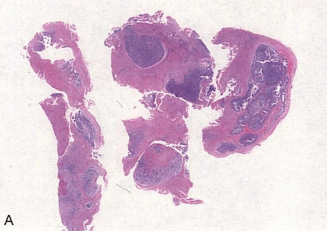

患者女,45岁。1年前发现左大腿后侧包块,质韧,活动差。1年来,包块逐渐增大,并出现疼痛。查体:左大腿后侧可见3cm×3cm包块,质韧,边界清,活动差。超声:左侧腘窝上方见一混合回声团块,大小:23mm×23mm,边界欠清。镜下观察包块形态如图所示。